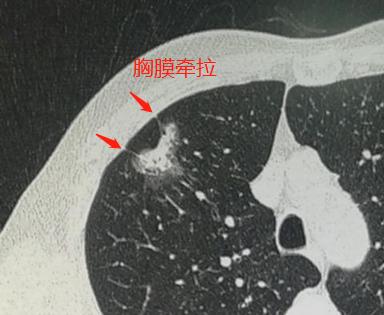

同时还可以看到线样的胸膜牵拉:

阅读过豪大夫肺结节系列的读者朋友,可能就会想到一个诊断要点:混合磨玻璃结节伴有胸膜牵拉,符合肺腺癌。

很遗憾,不属于,他的病灶接近3厘米了,并且伴有较多实性成分和胸膜牵拉。

据统计,这种线样的胸膜牵拉,侵犯胸膜的几率大约是20%。

诊断混合性磨玻璃结节侵犯胸膜的依据:

同时具备:病灶与胸膜相贴,直径大于2厘米,实性成分大于50%,局部胸膜增厚,则胸膜受侵的几率为99.2%。